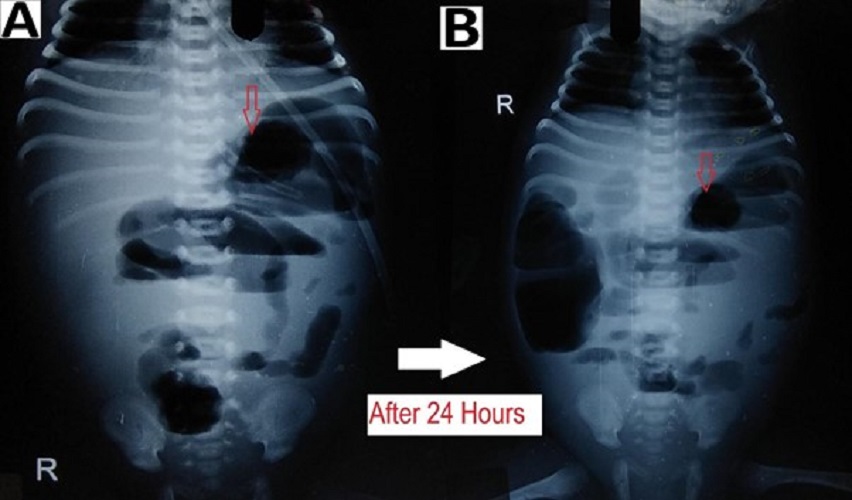

Figure 4

Preoperative radiographs showing: (A) increased bowel wall thickening (red arrow) and (B) dilated small bowel loops in the upper abdomen with ground glass appearance in the lower abdomen (below the red line).

Intestinal distension, often secondary to obstruction, is the most common sign visible in 90% of radiograms in neonates with NEC.[2] Although no evidence-based guidelines are available regarding the duration and frequency of radiographic examination, an attempt was made by Coursey et al. in 2009 using a ten-point scale for abnormal radiographic findings in infants with clinically suspected NEC.[24] They called it Duke’s Abdominal Assessment Scale (DAAS score). Findings of fixed (unchanging) bowel loops, definite pneumatosis, or portal venous gas as revealed by DAAS scores of 7, 8, or 9 were highly associated with eventual surgical intervention for suspected NEC.[25] Bowel wall thickening from oedema and haemorrhage is seen as separated bowel loops on radiographs. [15] Increased bowel wall thickening on radiographs in presence of clinical features is an early sign of NEC (Fig. 4). A wall thickness greater than 2.6 mm is a pathological finding on ultrasound. [21]

When intraperitoneal fluid is present in the abdomen, the gas-filled loops of the bowel float centrally in the abdomen and are separated from each other by the fluid. [15] In case of ascites (without pneumoperitoneum) due to small bowel perforation in NEC, the peritoneal fluid settles in the lower abdomen with relatively few small bowel loops in the upper abdomen (Fig. 4). Ultrasound is more sensitive and specific for diagnosing intraperitoneal fluid; whether it is free in the peritoneal cavity or a more localized fluid collection. The presence of echogenic ascites or septations within the fluid is highly suggestive of perforation.[2]